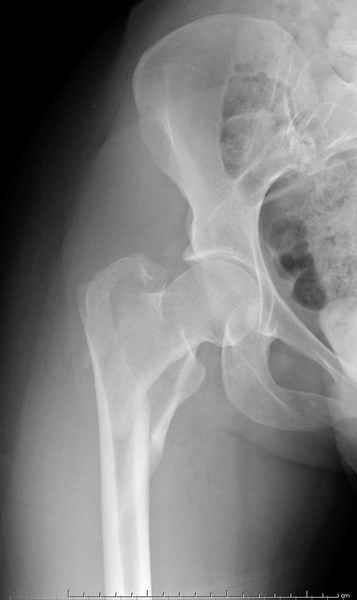

Уважаемые коллеги.Ко мне обратился мой коллега, весьма опытный травматолог, владеющий практически всеми видами остеосинтеза, с просьбой собрать мнения по поводу нескольких клинических случаев - два перелома бедра и перелом плеча.Если можно, подтвердите свое мнение иллюстрациями аналогичных ситуаций, либо ссылками - для клинического разбора. Бедро 1:Женщина 1929 г.р. Травма в результате падения 14.09.04г.Диагноз Закрытый оскольчатый чрезвертельный перелом правой бедренной кости со смещением отломков.Сопутствующие заболевания: ИБС, стенокардия напряжения, постинфарктный кардиосклероз (ИМ в 1992 году); гипертоническая болезнь 2 ст.; ожирение 3. Дополнительные данные - сохранная старушка.Спасибо.С уважением Александр Артемьев

Это 4-фрагментный перелом, традиционно-современная фиксация - это динамический бедренный винт, DHS. Либо какой-либо из проксимальных бедренных гвоздей, предназначенных для ранней полной нагрузки, из-за меньшего доступа, других преимуществ перед DHS нет. Если доступен только реконструкционный гвоздь, то винты вводить надо очень точно и аккуратно субхондрально, т.е. максимальной длины, а то прорежутся в головке.

Типичный остеопорозный вертельный перелом , не стабильный, 4-х фрагментный, базоцервикальный. Лечение оперативное не позднее 48 часов после перелома, чем раньше тем лучше, если общее состояние позволяет.

Фиксатор или DHS 130 градусов или PFN с короткой ножкой. Если DHS, то шуруп должен находиться в центре шейки и дополнительно еще простой длинный шуруп против ротации в проксимальной части шейки над шурупом DHS. Полную нагрузку на ногу начать через 6 недель.